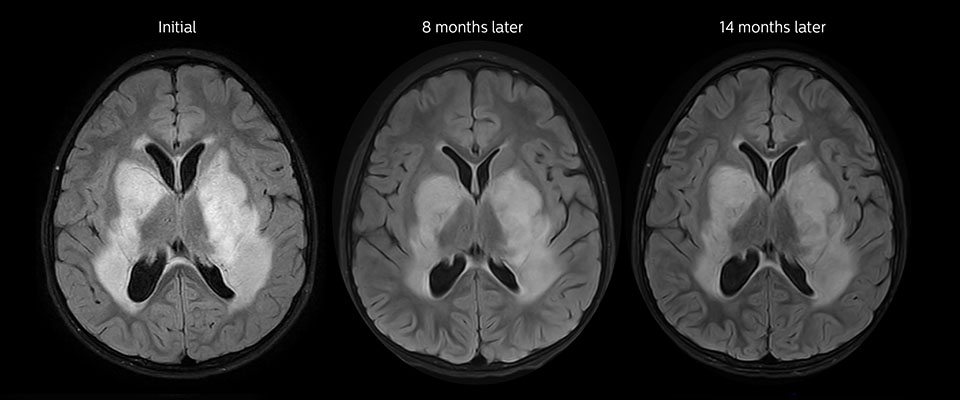

MRT mit APT nach der Resektion

Unmittelbar nach der Resektion wurde erneut eine MRT durchgeführt. Die T2-gewichteten und kontrastverstärkten T1-gewichteten Bilder lassen keine eindeutige Unterscheidung von Residualtumorgewebe und postoperativen Gewebeveränderungen zu. Auf dem APT-Bild ist noch ein hohes Signal zu sehen, das auf Residualtumorgewebe hindeuten würde.

Nachuntersuchung im Laufe der Zeit

In späteren Nachuntersuchungsscans weisen die kontrastverstärkten T1-gewichteten Bilder auf rezidivierendes Tumorwachstum hin. Daher wäre es interessant, den prädiktiven Wert von APT in einer grossen Patientengruppe zu untersuchen.